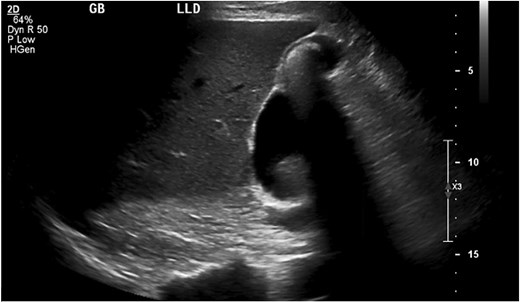

An abdominal ultrasound (Fig. 1), obtained before his first clinic visit, showed echogenic densities with shadowing in the gallbladder wall consistent with cholelithiasis. Review of the imaging revealed a stalked lesion communicating with the gallbladder, later confirmed as a PGA. In clinic, he was counseled that his pain was atypical for biliary colic and that a cholecystectomy might not resolve his symptoms. Nonetheless, because the pain was debilitating and impacted his ability to work, he opted for an elective cholecystectomy.

Ultrasound of gallbladder with the pyloric gland adenoma in view.